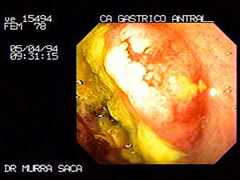

Paciente Femenino de 62 años:

Quien fue tratada por adolecer de anemia por un año sin hacerle ningún estudio, solamente le inyectaban hierro, por vez primera acude a la consulta con historia de haber perdido más de 20 libras y dolor abdominal acompañado de vómitos se le procedió a practicar el estudio de endoscopia detectándosele un intenso carcinoma del antro gástrico. El día de dicho estudio fue unas horas antes del gran terremoto el 13 de Enero 2001.